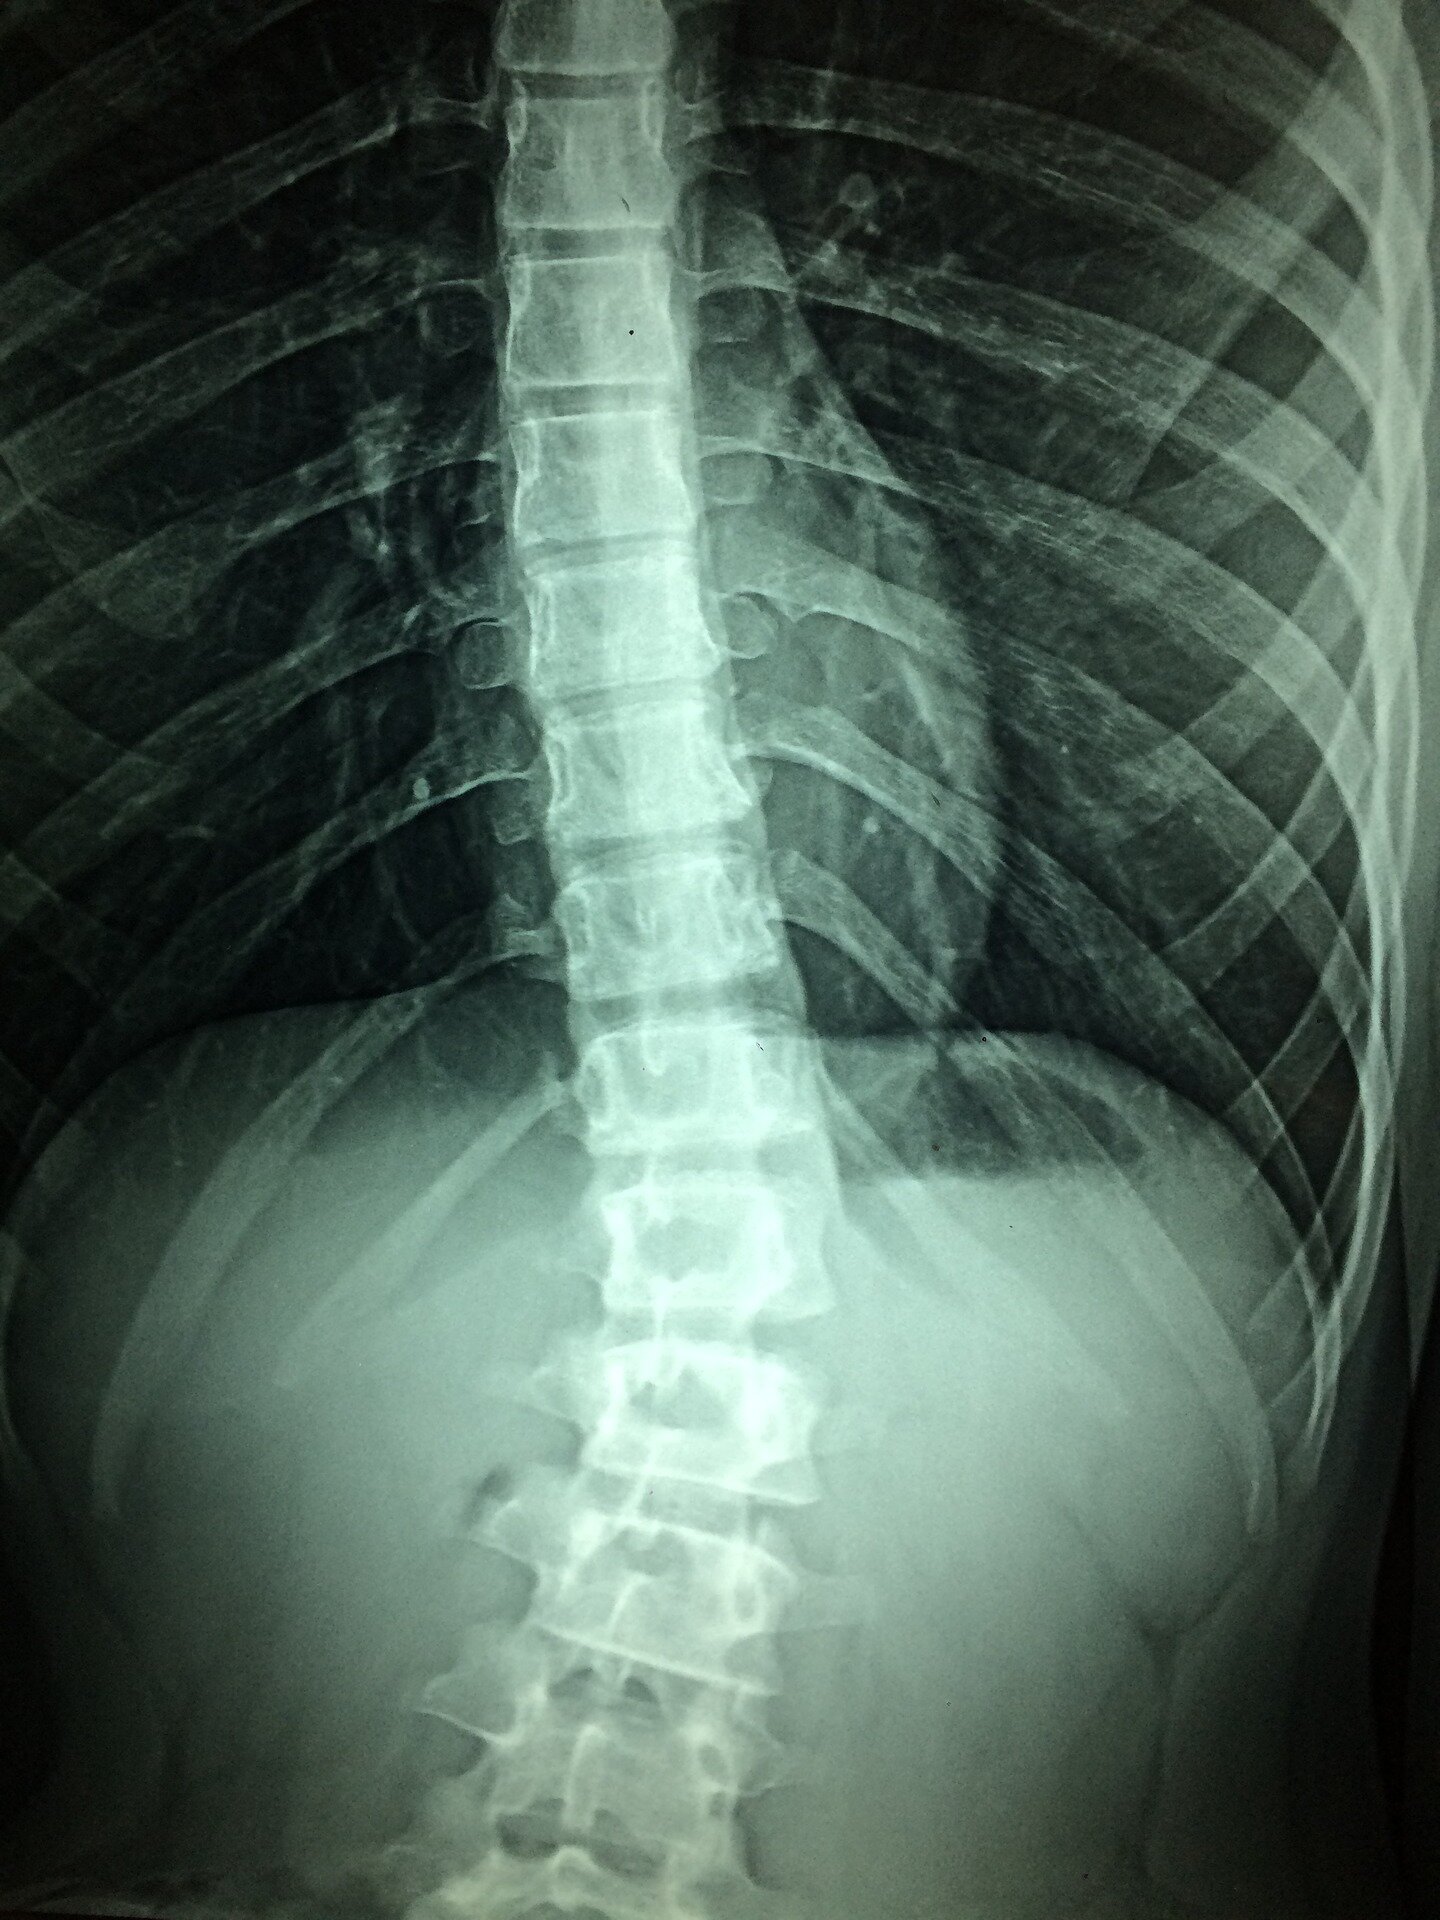

Scientists regenerate neurons that restore walking in mice after paralysis from spinal cord injury::In a new study in mice, a team of researchers from UCLA, the Swiss Federal Institute of Technology, and Harvard University have uncovered a crucial component for restoring functional activity after spinal cord injury. The neuroscientists have shown that re-growing specific neurons back to their natural target regions led to recovery, while random regrowth was not effective.